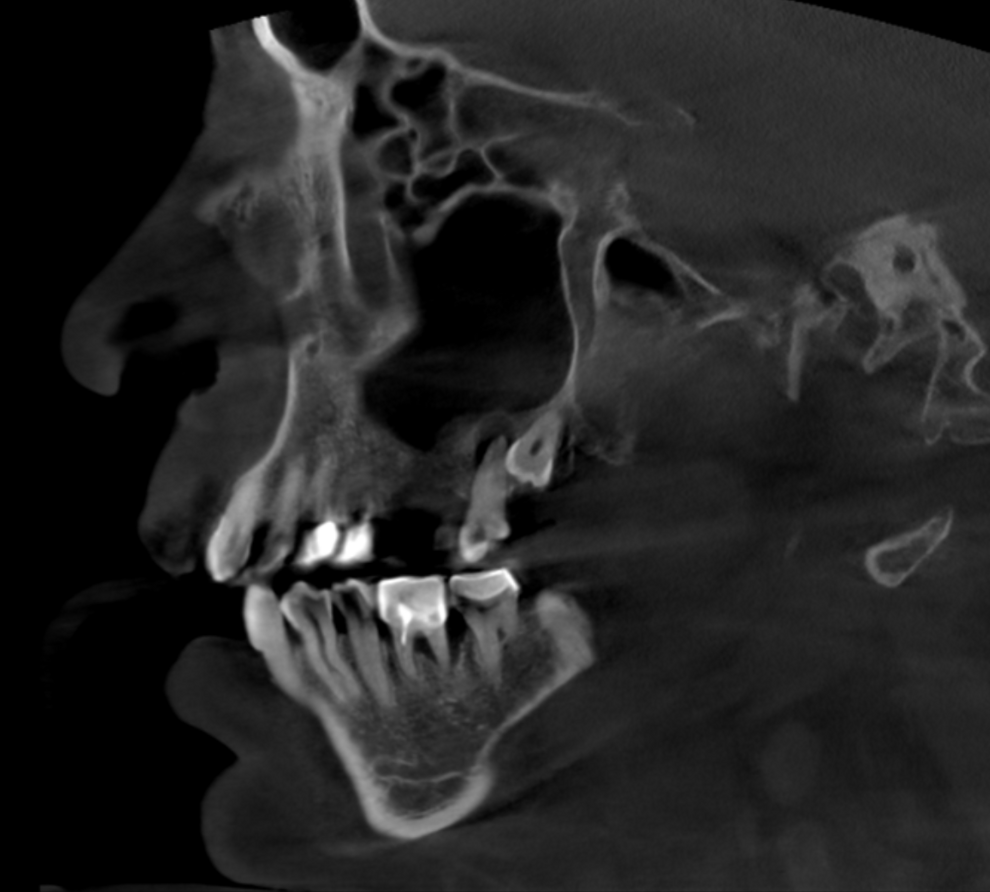

Figs. 1a & b: Initial small-volume CBCT scan, panoramic view (a) and cross-section of tooth #17 (b).

The 61-year-old male patient wanted to have his missing maxillary right teeth replaced with implants. After examination by an implantologist, he was referred to our dental office for further dental treatment because of the findings of a small-volume CBCT scan taken: advanced inflammation and bone loss were visible in the periodontal tissue of the maxillary right second molar and severe maxillary sinusitis was observed (Figs. 1a & b).